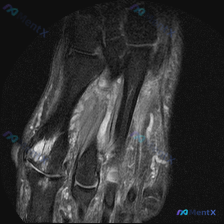

今天遇到一个挺有意思的病例,用户提示存在半月板异常,但只提供了单张膝关节MRI T1冠状位图像,整理一下分析思路分享给大家。 一、病例/影像基本信息 提供的单张膝关节MRI T1冠状位图像分析结果如下: 1. 骨骼结构:股骨远端、胫骨近端、腓骨近端轮廓清晰,骨髓信号正常,未见局灶性骨质破坏或异常信号...

今天整理一份很有代表性的膝关节MRI读片病例,和大家分享一下思路。这个病例最初是被怀疑有半月板异常,我们一起来看看实际情况。 病例影像基本信息 这是一份膝关节MRI冠状位T2加权图像,我们先梳理所有基础观察: 1. 股骨远端、胫骨近端骨髓信号正常,没有明显骨髓水肿 2. 半月板情况:内侧半月板体部形...